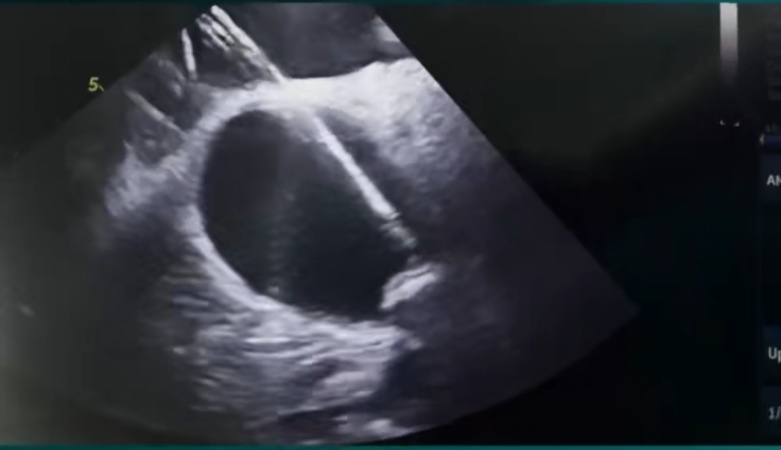

团队率先为患者实施全麻下房颤射频消融术,随后,经ICE实时引导,将Watchman FLX封堵器精准释放在左心耳开口处,术后造影及超声验证封堵完全无残余分流。

Carto三维系统结合ICE技术,既能提升消融精准度、降低并发症,又可动态评估左心耳形态,确保封堵器完美贴合,尤其适用于左心耳结构复杂或需个体化治疗的患者。